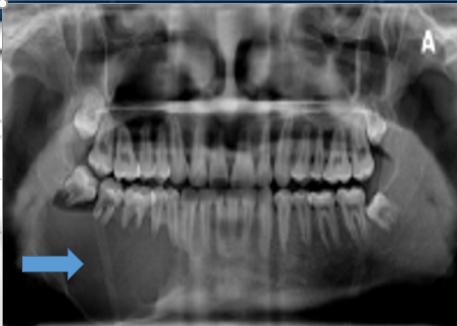

巨大的颌骨囊肿

颌骨囊肿开窗减压术,临床效果较好

当发现了骨头上出现黑洞,不要惊慌,也不要担心是否患上了癌症。我们需要积极的面对问题,早期处置,即使很大的颌骨囊肿,有数据研究证明,也会取得良好的效果!

1、囊肿刮治(a组)、刮治+植骨(b组)、开窗减压术(c组)比较,术后9-12月,囊肿缩小体积c组明显大于a、b两组,差异有统计学意义[1]。

2、与囊肿刮治术相比,开窗减压术能够减轻对恒牙胚及年轻恒牙的损伤,促进囊腔愈合[2]。

3、开窗减压术,切口小,耗时少,不会明显影响面部美观,具有较优疗效[3]。